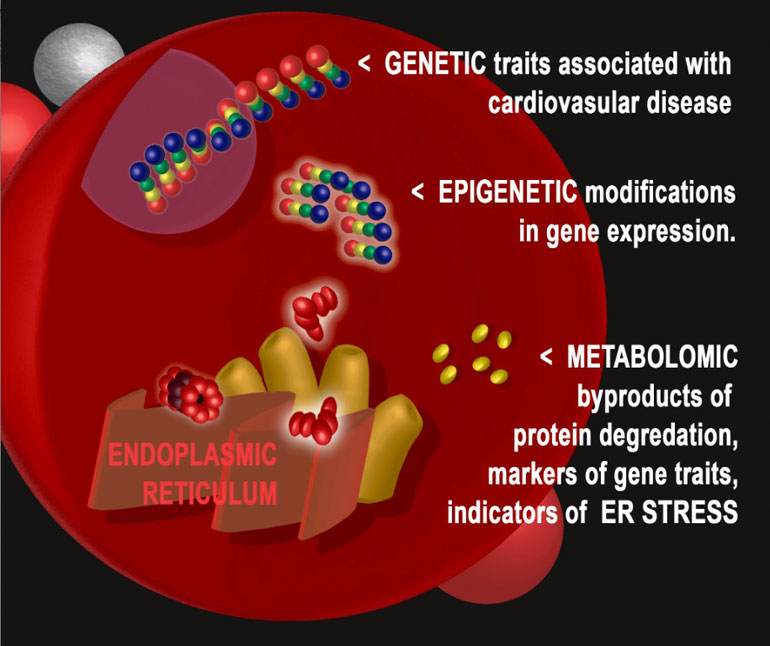

Комбинированное использование исследовательских инструментов генетики, транскриптомики, эпигенетики и метаболомики позволило ученым университета Дьюка, работающим под руководством

Оказалось, что стрессовое воздействие на клеточную структуру, известную как эндоплазматический ретикулум, ассоциировано с риском развития в будущем

По словам доктора Шах, специалистам давно известно о существовании взаимосвязи между стрессом эндоплазматического ретикулума и целым рядом заболеваний, в том числе диабетом 1 типа и болезнью Паркинсона. Однако полученные данные впервые указывают на то, что этому механизму принадлежит определенная роль в развитии инфаркта миокарда и смерти от заболеваний сердца. Более того, весьма многообещающе выглядит продемонстрированная возможность оценивать уровень стресса эндоплазматического ретикулума путем анализа одной капли крови, что указывает на возможность профилактического вмешательства и снижения риска развития основных болезней

Даже после завершения картирования генома человека и идентификации генетических признаков, ассоциированных с

Доктор Шах поясняет, что генетический анализ разделяет людей на группы, обладающие теми или иными признаками. Однако очевидно, что если есть два человека с одним и тем же признаком, при этом один из них имеет лишний вес, курит и ведет нездоровый образ жизни,

Исследователи посвятили свою работу поиску промежуточных продуктов, соединяющих гены и механизмы, лежащие в основе развития заболеваний. Для этого они привлекли метод метаболомики — анализа метаболитов или содержащихся в организме в следовых количествах побочных продуктов протекающих в клетках процессов.

Для этого они провели полногеномный анализ уровней комплекса специфичных метаболитов у 3 700 пациентов, направленных на катетеризацию сердца. В своей более ранней работе ученые установили, что эти метаболиты являются прогностическими факторами для заболеваний

После этого авторы прибегли к эпигенетическому и транскриптомному подхода для выявления различий между пациентами с высокими и низкими уровнями метаболитов. В данном случае ключевым компонентов снова оказался механизм, запускаемый стрессом эндоплазматического ретикулума.

Таким образом использование многоплатформенного «-омного» подхода позволило идентифицировать ранее неизвестные генетические варианты, ассоциированные с уровнями метаболитов и развитием заболеваний